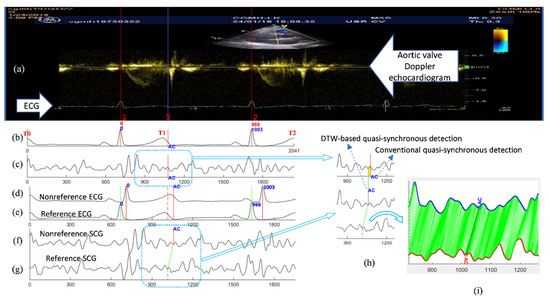

The DTW-base quasi-synchronous alignment introduces two modifications to the conventional quasi-synchronous alignment: (1) the intermediary reference signal pair, and (2) DTW-based point-to-point alignment of two signal sequences. The examples and comparison of SCG fiducial point detections in the nonreference SCG signal using the conventional and DTW-based quasi-synchronous alignment methods are demonstrated in Figure 7. Figure 7a–c illustrate the conventional approach, whereas Figure 7d–g display the DTW-based approach. The echocardiogram shown in Figure 7a is a color Doppler flow measurement at the aortic valve. In Figure 7a, the 966-ms period between R1 and R2 is selected as the synchronization target. The signals in Figure 7b,d represent the same nonreference ECG signal, whereas Figure 7b is rescaled (squeezed to fit signal length of 1003 ms to 966 ms) and shifted such that it can be visually aligned to the ECG R1-R2 section in Figure 7a. The signals in Figure 7c,f represent the same SCG signal (other than the reference SCG signal). Figure 7c has been rescaled and synchronized to Figure 7b.

A reference signal pair of ECG and SCG was sorted out with the RR interval closest to the R1–R2 period. In this example, the reference signal pair had a heartbeat cycle of 966 ms. Shifting, but not rescaling, was required to align the reference signals until the ECG R peaks matched R1 and R2, as shown in Figure 7e,g. Referring to the condition in Figure 4, the ECG signals in Figure 7a,e, as well as the echocardiogram and SCG signal in Figure 7g, are postulated to align to each other (within the RR interval) spontaneously. The fiducial point AC was detected in the reference SCG signal by extending the blue line from Figure 7a–g. The fiducial point AC was projected from the reference SCG signal (Figure 7g) to nonreference SCG signal (Figure 7f) with the aid of a DTW-based software program, as shown in Figure 7f–i.

As mentioned earlier, a fiducial point detection error resulted from the signal rescaling manipulation in the conventional quasi-synchronous alignment, as indicated by the width of the yellow rectangle in Figure 7h. Figure 7i displays the results of DTW point-to-point alignment with the new cost function between the reference SCG signal (red) and the target nonreference signal (blue).

Figure 7. Illustrations and comparison of the fiducial point detection in the nonreference SCG signal between the methods of the conventional and the DTW-based quasi-synchronous alignment: (a) Doppler echocardiogram image with the identified ECG R peaks (R1, R2) and aortic valve closing (AC) event; (b) ECG alignment (to the ECG signal in the echocardiogram) under the conventional quasi-synchronization (aligned through shifting and rescaling); (c) SCG signal (synchronous to (b)) aligned by the conventional approach with the fiducial point AC detected by virtual line extending from the echocardiogram; (d) Nonreference ECG signal (no need for R peaks alignment to other ECG signal); (e) Reference ECG signal with R peaks aligned to ECG R peaks in the echocardiogram R1 and R2 (aligned by shifting only) under DTW-based quasi-synchronous alignment; (f) Nonreference SCG signal (synchronous to (d)) with the fiducial point AC projected by DTW-based quasi-synchronous alignment; (g) Reference SCG signal (synchronous to (e)) aligned to echocardiogram with the fiducial point AC detected by virtual line extending from the echocardiogram under DTW-based approach; (h) The detection error (indicated by the width of yellow rectangle in the upper graph) of the conventional method illustrated by comparing the AC points detected from conventional quasi-synchronous alignment (upper trace) and DTW-based (middle trace) approach; (i) Point-to-point mapping of the nonreference SCG signal (upper trace) with the reference SCG signal (lower trace) under DTW alignment.